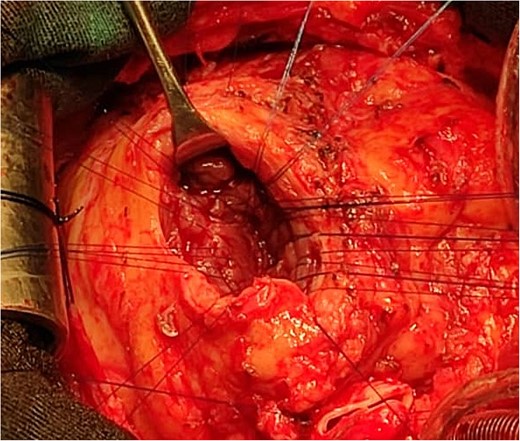

An 11-year-old girl was referred to our hospital with a main complaint of progressive exertional dyspnea. She had undergone surgical repair of SAS 6 years ago. Transthoracic echocardiogram (TTE) revealed the following findings: severe left ventricular hypertrophy, tunnel-like fibromembranous subaortic stenosis with a length of 10 mm, a peak gradient (PG) across the LVOT of 170 mmHg, and mild aortic regurgitation. Based on these findings, the patient was scheduled for elective surgical repair with a possible indication for MKO. The operation was performed via median sternotomy with great caution to avoid inadvertent rupture of any cardiac cavity due to heavy adhesions from the previous operation. The aorta was cannulated just below the takeoff of the innominate artery. Bicaval cannulation was performed to provide a bloodless field. Aortic cross-clamping was applied, and antegrade cold blood cardioplegic solution was administered via a catheter placed in the ascending aorta. The ascending aorta was opened transversely 1 cm above the sinotubular junction (Fig. 1). The aortic valve leaflets were examined carefully to confirm that the aortic valve could be preserved. LVOT was examined thoroughly, and it was clear that the stenosis in the subaortic area was so complex that simple resection through the aortic valve orifice would not be sufficient. The right ventricular outflow tract was opened transversely below the pulmonary valve. The conal papillary muscle was identified (Fig. 2). A right-angle instrument was introduced through the aortic orifice into the interventricular septum, and the tip of the instrument was used to perforate the conal septum to the left of the conal papillary muscle to prevent damage to the conduction system; the septal incision was completed with great caution to avoid damage to the aortic cusps and to extend the incision downward as necessary to completely relieve the stenotic subaortic area (Fig. 3). Interrupted 5/0 Prolene sutures were placed circumferentially around the septal incision to close the interventricular septal defect using a bovine pericardial patch to provide adequate widening of LVOT (Fig. 4). The right ventriculotomy was closed with a second bovine pericardial patch to avoid any possible obstruction of the right ventricular outflow tract (Fig. 5). The remainder of the operation was completed uneventfully. After 6 hours of mechanical ventilation, the patient was extubated, and she convalesced well postoperatively. TTE showed excellent results of the operation with PG across LVOT of 20 mmHg. On 1 year follow-up, the patient was asymptomatic and in very good general condition, and TTE findings confirmed the excellent result.

Intraoperative image showing the bovine pericardial patch used to close the septal incision. (1) Right ventriculotomy and (2) bovine pericardial patch.